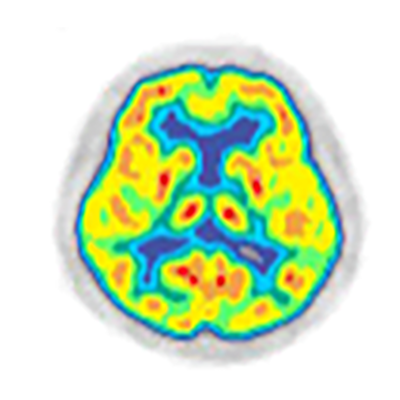

⑦認知症の診断に役立ちます

FDG-PET検査はがんの検査として注目されていますが、もとは脳の働きを調べる研究からはじまった検査方法です。

脳のエネルギー代謝や神経細胞活動の活動状態を調べることを得意とします。

特にアルツハイマー型認知症では記憶を司るところの活動が低下するためPET検査で比較的早期に発見することができます。

認知症検査としてはアミロイドPET検査も準備しています。

脳 PET(FDG)の横断図

側頭頭頂葉連合野の代謝低下が見られます。ブドウ糖の取込の度合いが記憶や理解力に関係する部位で低下するのがこの病気の特徴です。